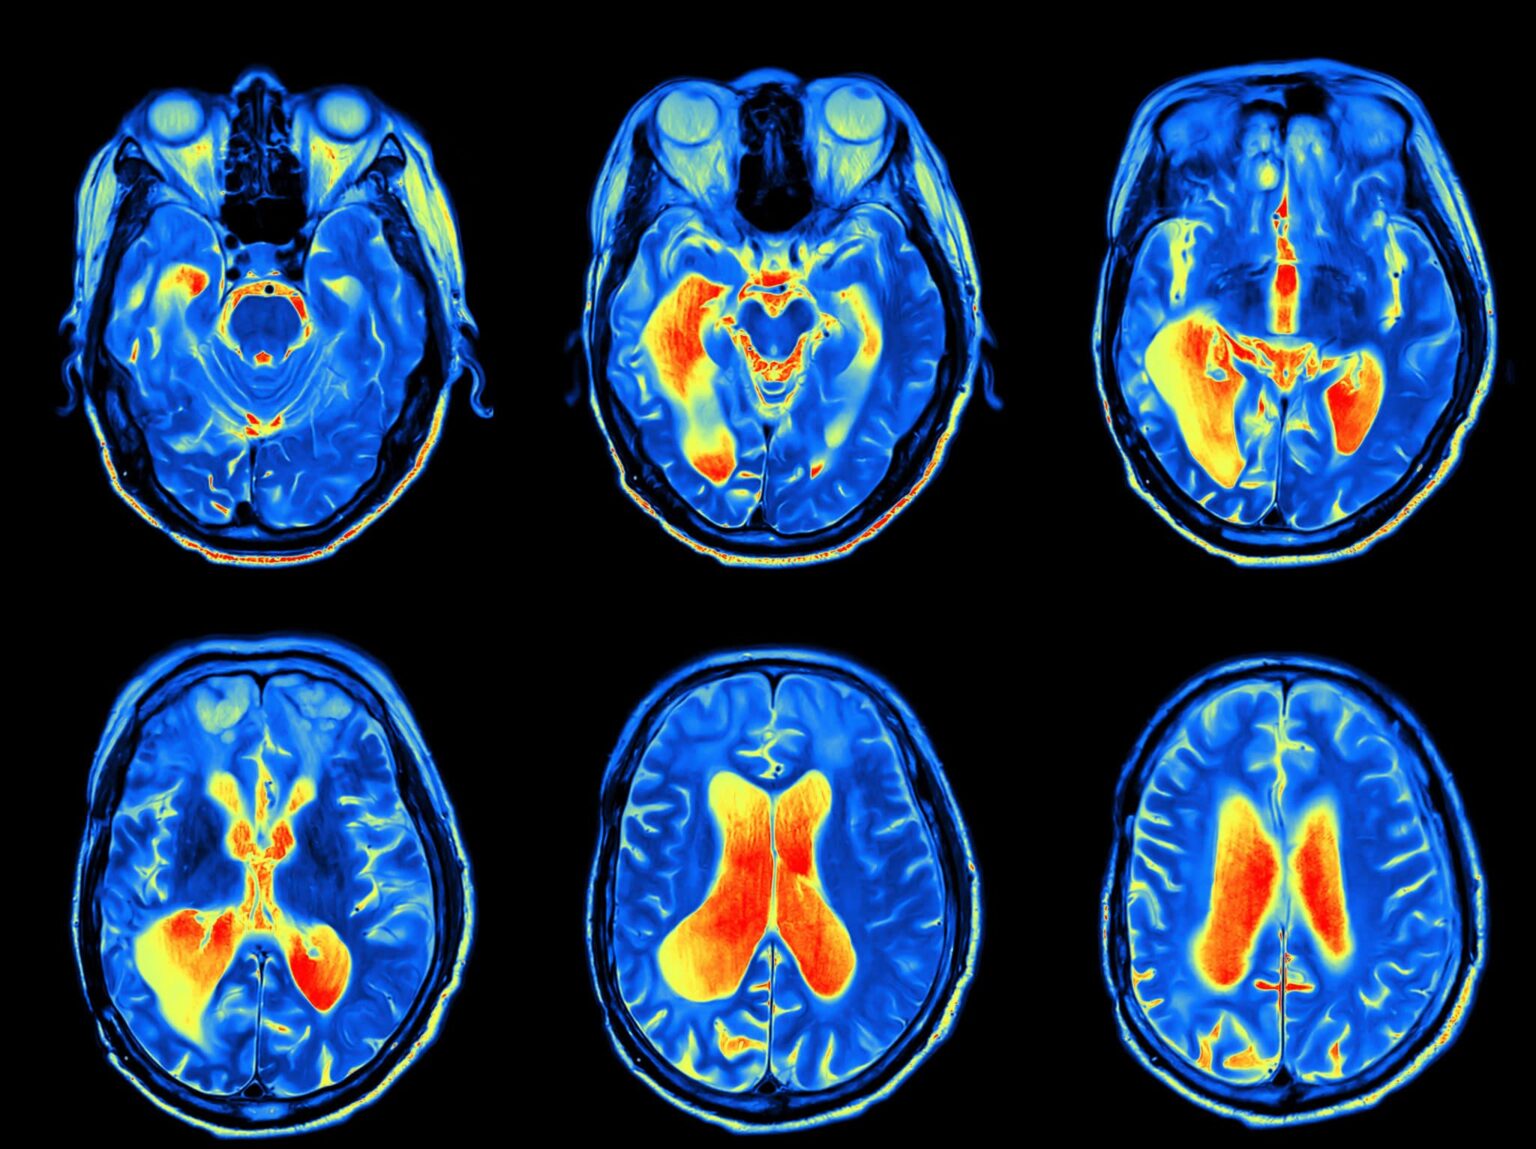

A series of MRI images of the brain during a skull base tumor exam.

• MRI